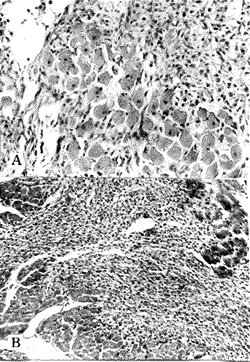

A-光镜下大鼠心肌梗死灶较局限,梗死灶内可呈岛屿

状分布的存活心肌细胞,肉芽组织增生活跃。HE,×100; B-光镜下大鼠心肌梗死灶仅限于心内膜下,梗死灶内可见存活的心肌细胞,梗死灶大部分已被肉芽组织机化。HE,×100

图2 心复康组